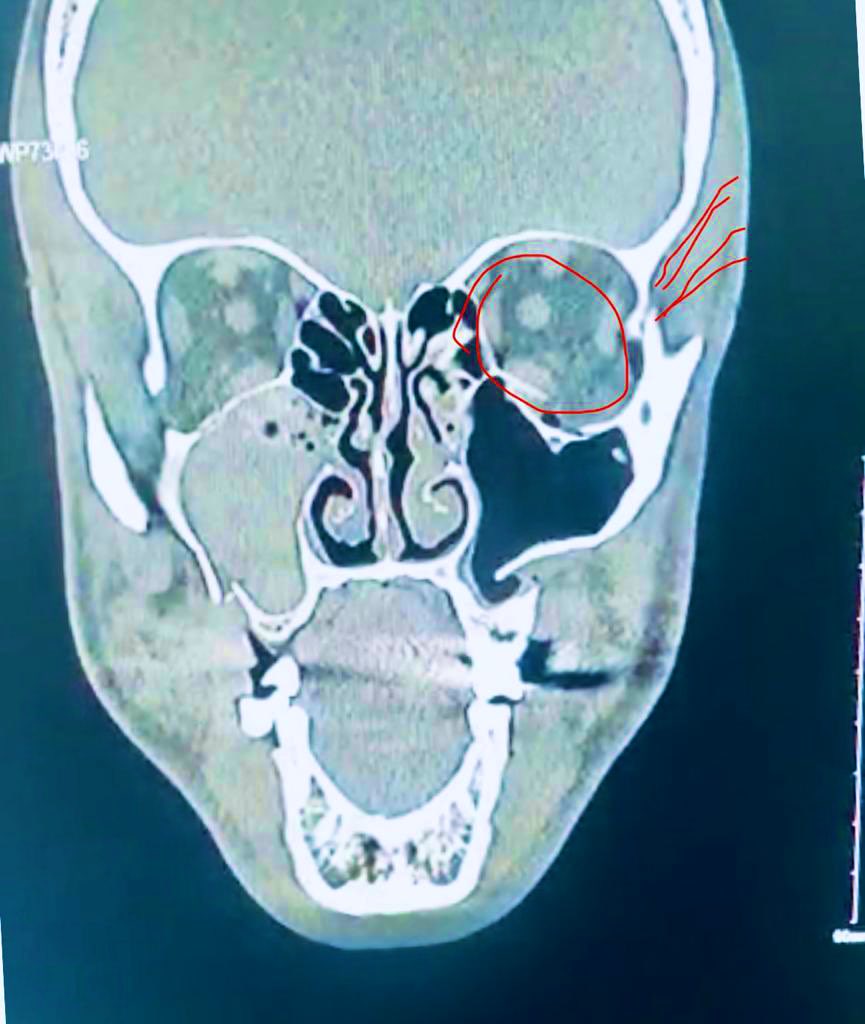

ملخص الاصابه هو كسر في الانف و الفك العلوي و محجر العين و العظمة الرباعية لزاوية العين و الوجنة اليسرى.

وتمت ارجاعهم الى مكانهم الطبيعي مع تثبيت بمشابك في منطقة الفك فقط. اما العين و العظام التي حولها فتم بطريقة و ضع عظم في مناطق الكسر و كذالك استخدام مادة لاصقة العظم. و تم هذا عن طريق شق داخلي من داخل العين.